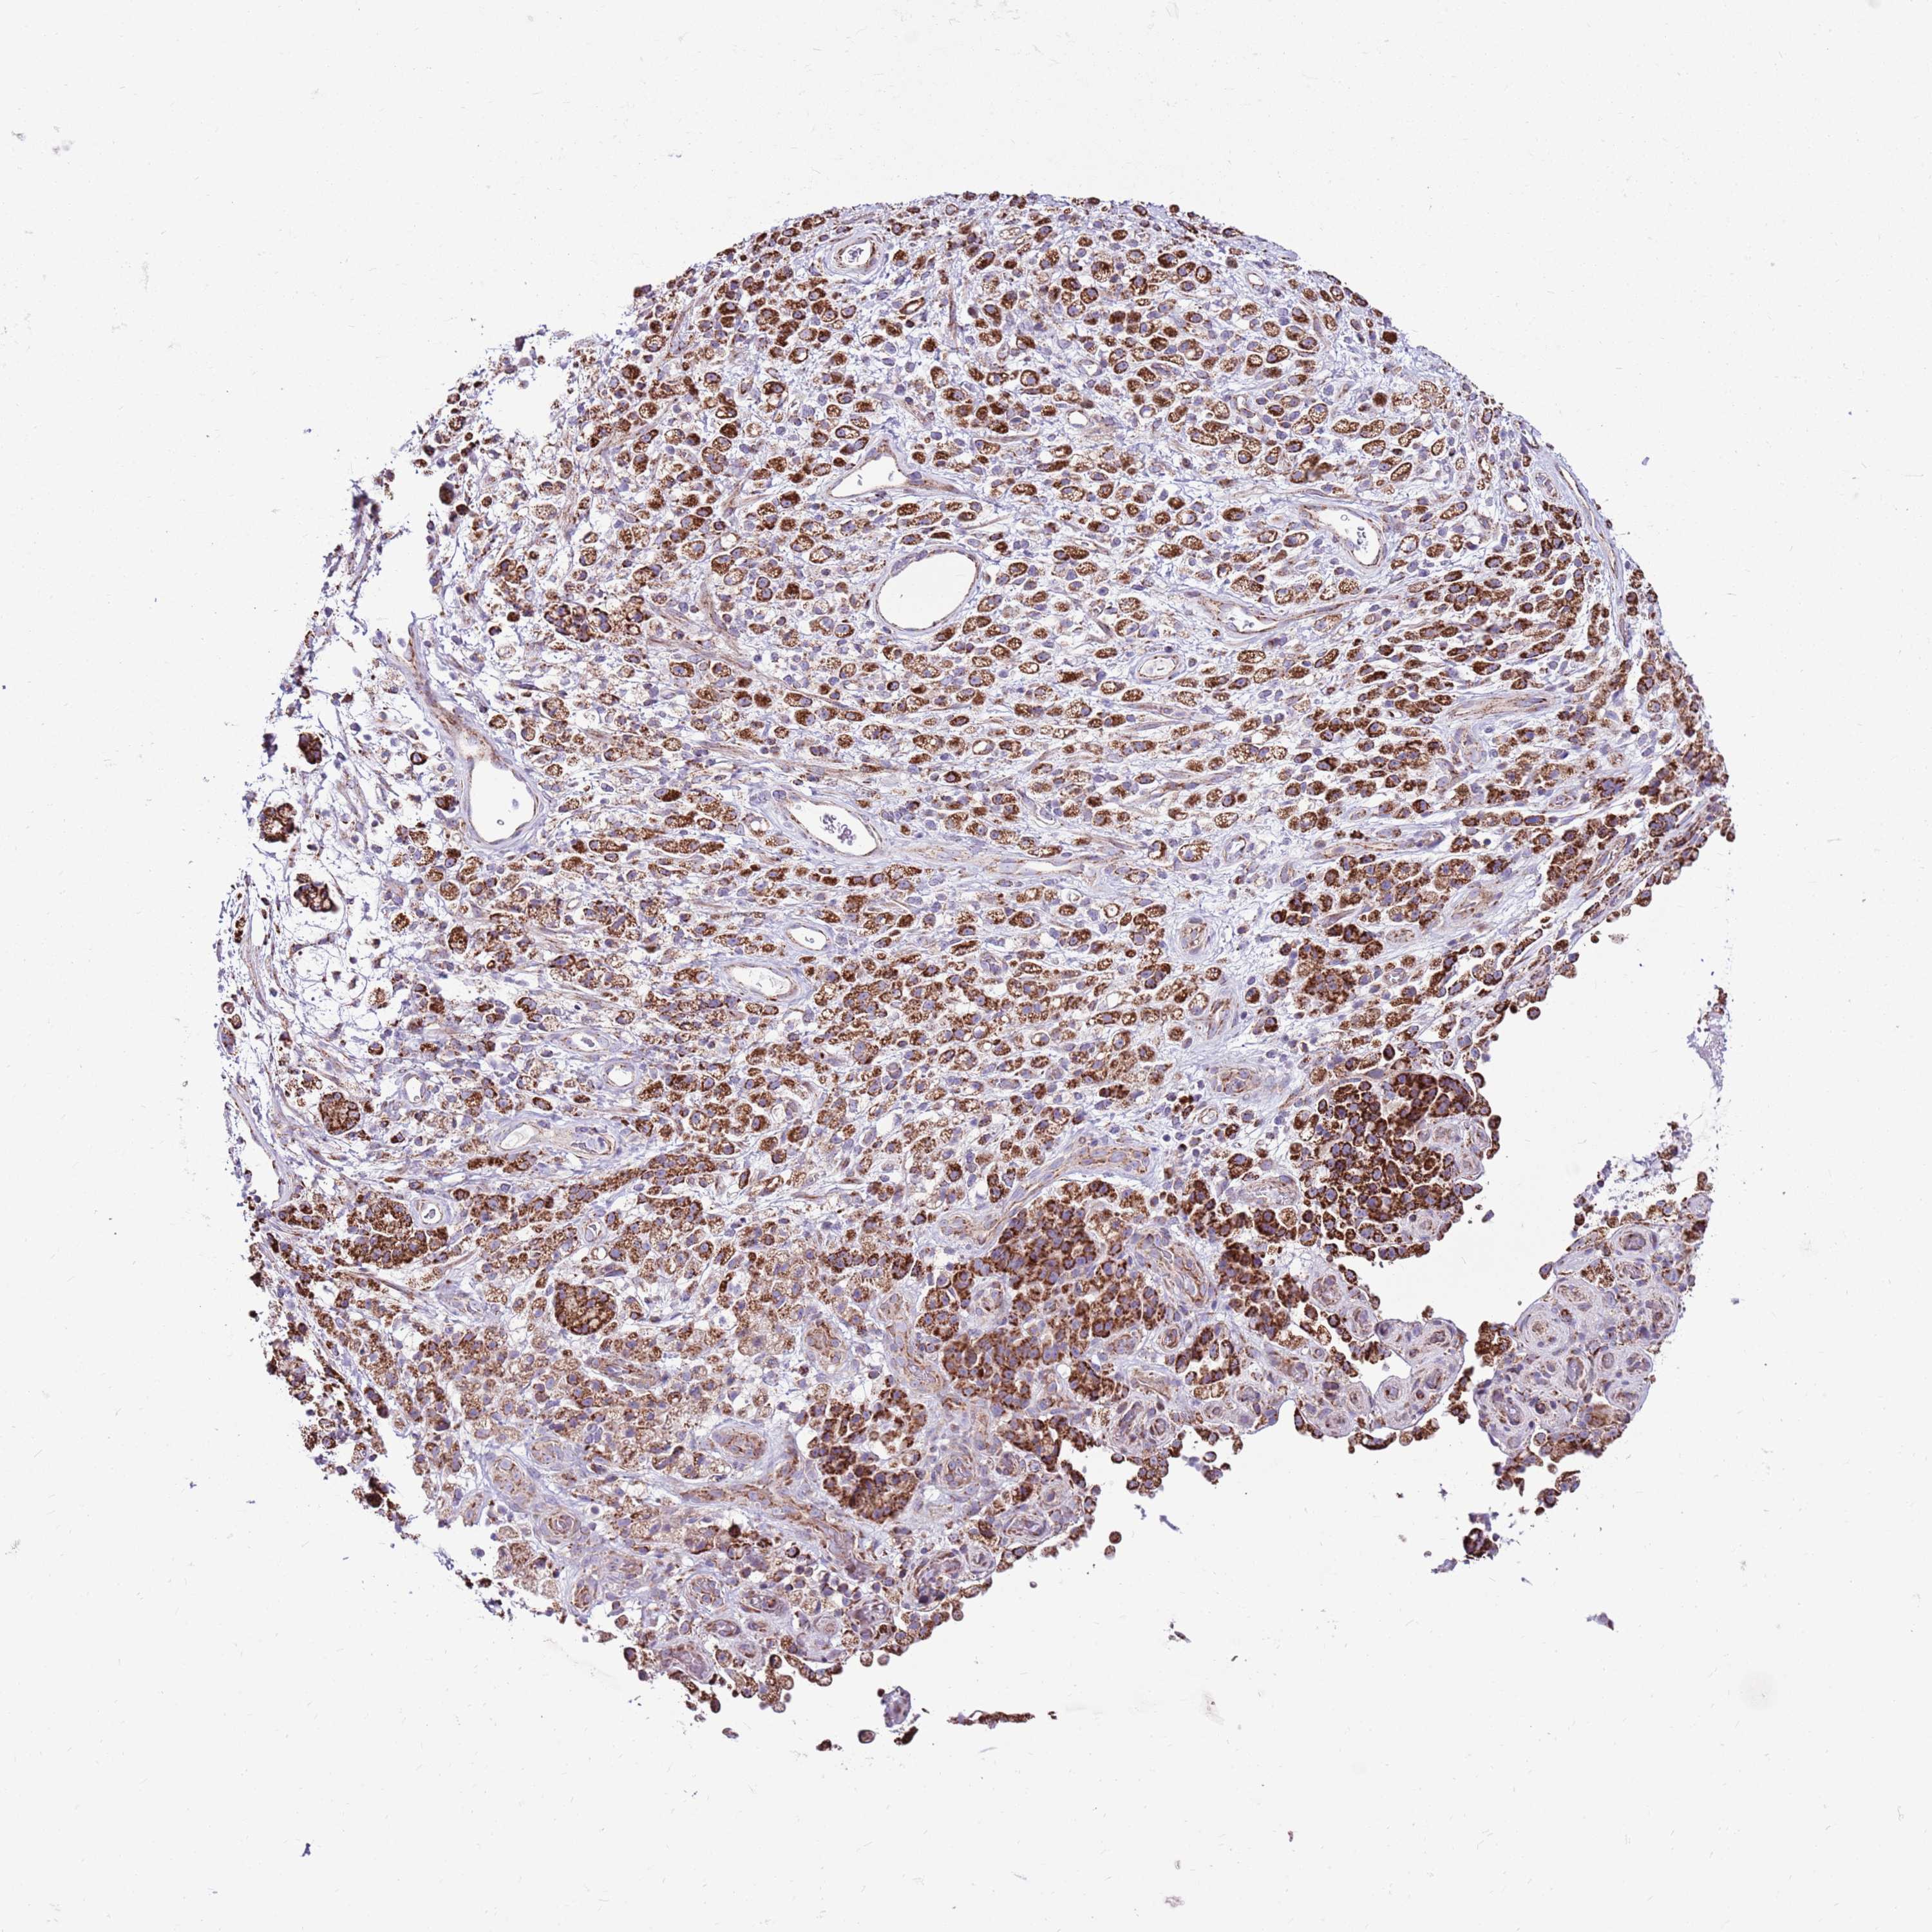

STOMACH CANCER - Protein expressioni

A mouse-over function shows sample information and annotation data. Click on an image to view it in a full screen mode. Samples can be filtered based on level of antibody staining by selecting one or several of the following categories: high, medium, low and not detected. The assay and annotation is described here.

Note that samples used for immunohistochemistry by the Human Protein Atlas do not correspond to samples in the TCGA dataset.

Antibody stainingi

Antibody staining in the annotated cell types in the current human tissue is reported as not detected, low, medium, or high, based on conventional immunohistochemistry profiling in selected tissues. This score is based on the combination of the staining intensity and fraction of stained cells.

Each image is clickable and will lead to virtual microscopy that enables deeper exploration of all samples and also displays staining intensity scores, fraction scores and subcellular localization as well as patient and tissue information for each sample.

Antibody HPA041062

Antibody HPA045473

Staining

High

Medium

Low

Not detected

Intensity

Strong

Moderate

Weak

Negative

Quantity

>75%

75%-25%

<25%

None

Location

Nuclear

Cytoplasmic/membranous

Cytoplasmic/membranous,nuclear

Adenocarcinoma, NOS